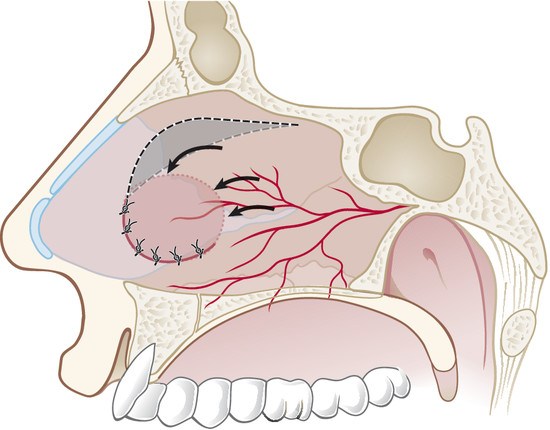

Through a hemitransfixion incision, mucoperichondrial and mucoperiosteal layers are extensively elevated on one side of the nasal septum, from the inferior edge of quadrilateral cartilage up to the choana, nasal floor, and 1 cm from the nasal roof (Fig. 19‑2).

On the other side, in oval perforation with horizontal major diameter, a horizontal incision as long as the perforation major diameter is performed by a sickle knife on nasal mucosa 1 cm to the dorsal border of septal cartilage. The mucoperichondrial flap is then elevated from the perforation margin up to the incision. The flap is thus transposed downward and the borders of the perforation are sutured together with a 3–0 Vicryl suture (Fig. 19‑3).

In the case of rounded perforations, a rotation/advancement mucoperiosteal flap is designed by a rounded incision based posteriorly on the nasal-septal artery and elevated up to 1 cm from the choana (Fig. 19‑4). Also, in this case the flap is rotated to reach the inferior border of the perforation and sutured with a 3–0 Vicryl suture (Fig. 19‑5).